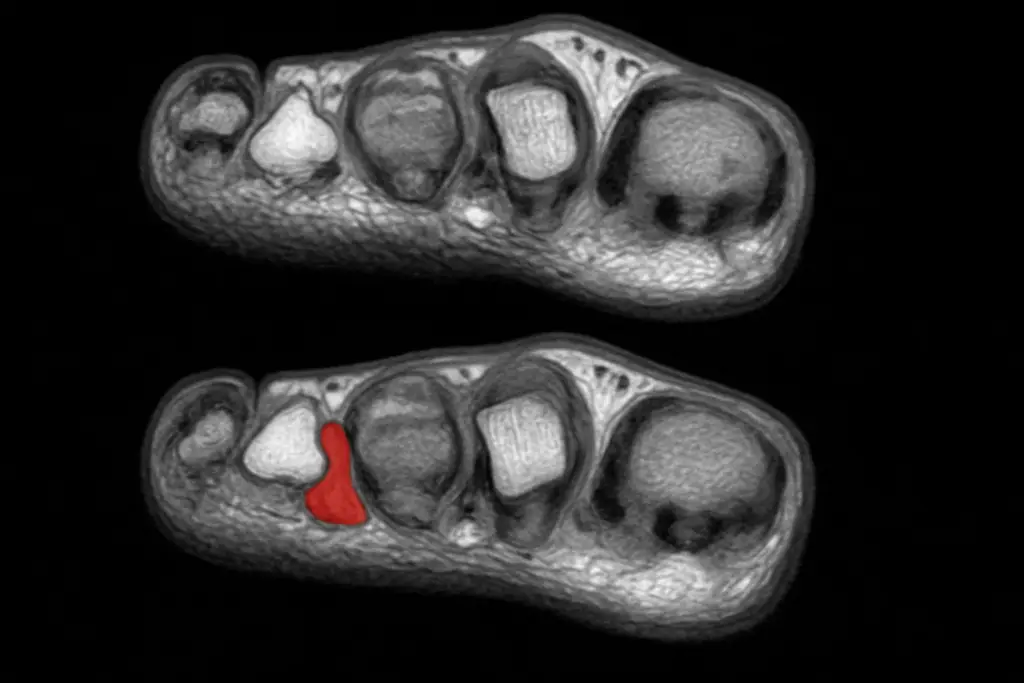

- Получить данные инструментальной диагностики. МРТ, рентген, УЗИ помогут заглянуть вглубь проблемы и точно установить причину болей и плохого самочувствия. Ниже пример, как выглядит неврома Мортона на фото.